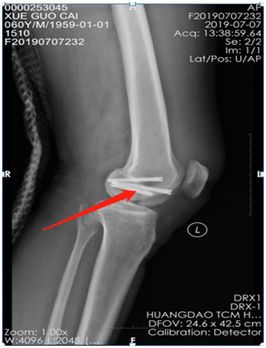

薛大叔左膝外侧有(以腓骨小头为中心)约10cmX15cm皮肤挫伤,其中间约5cmX8cm皮肤色紫,血运差;膝关节内上侧有约6cmX25cm皮肤挫伤,血运不满意 。医生为其进行了详细检查,确诊为左股骨内后髁骨折(Hoffa骨折)、左腓骨小头骨折、左膝内侧半月板损伤、左下肢挫裂伤 。

术前CT片